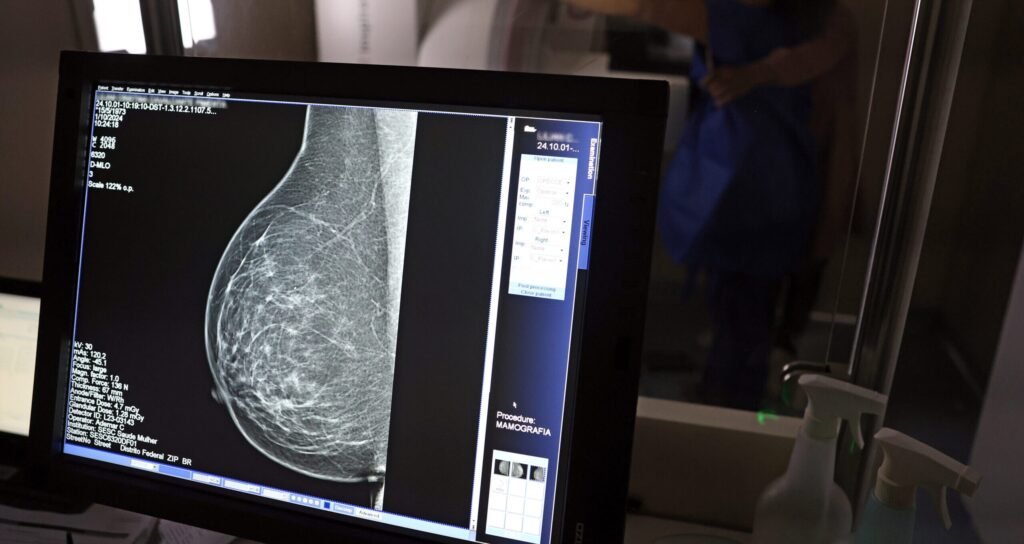

Caminhões da Mamografia: mais de 5 mil exames em janeiro

A saúde da mulher no Piauí ganha reforço importante com a chegada dos <strong>Caminhões da Mamografia</strong> ao Território do Vale dos Rios Piauí e Itaueira, uma ação essencial que faz parte do grande esforço para realizar mais de 5 mil exames em janeiro. Essa iniciativa, capitaneada pelo Governo do Piauí e executada pela Secretaria Estadual de Saúde (Sesapi), visa descentralizar o acesso a exames preventivos, levando o serviço diretamente às comunidades mais afastadas dos grandes centros urbanos.

Região Entre Rios

Os Caminhões da Mamografia, uma iniciativa crucial do Governo do Piauí e executada pela Secretaria Estadual de Saúde (Sesapi), intensificam sua atuação na Região Entre Rios durante o mês de janeiro. Com o objetivo de realizar um total de 5.403 exames em mulheres de 40 a 69 anos, a campanha chega a diversas localidades da zona rural de Teresina e culmina com uma abrangente agenda no município de Altos, reforçando o compromisso com a saúde feminina e a detecção precoce de doenças.